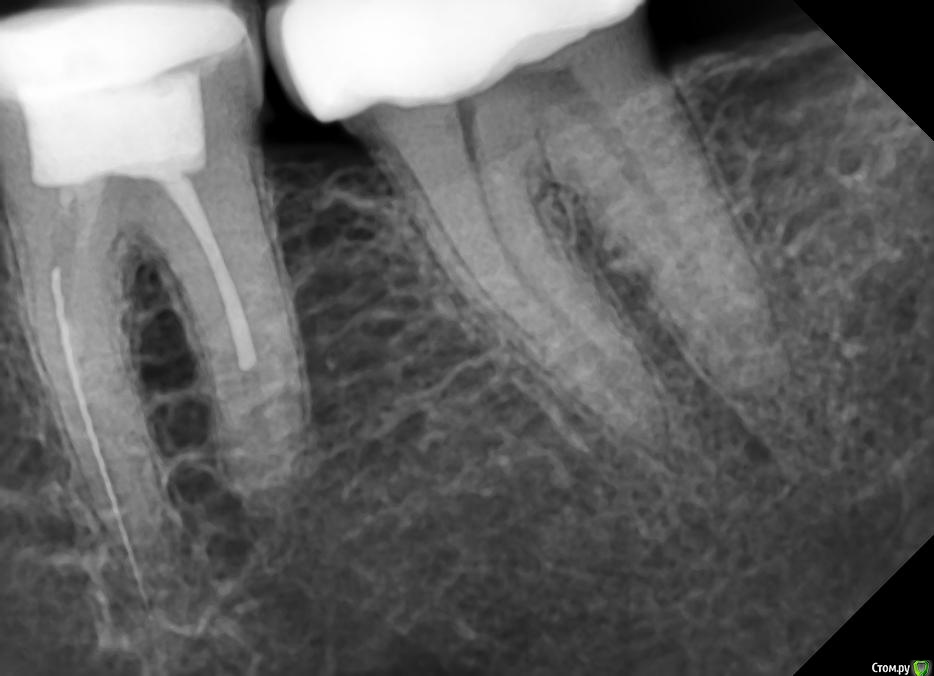

Slava76 Опубликовано 5 декабря, 2020 Поделиться Опубликовано 5 декабря, 2020 Всем доброго дня!Три дня назад с утра появилась боль в нижней челюсти слева. Сначала было не понятно, что болит зуб или мышцы. Но боль шла из под двух крайних коренных зубов. На крайнем зубе коронка, которую установил пару лет назад, зуб живой. У другого зуба пломба, которую установили около 10 лет назад, нервы удалены. Постучал чайной ложкой по этим зубам, боль не усилилась. От холодного, горячего боль так же не усиливается. К вечеру небольшая боль ощущалась только при сжимании зубов. На следующий день с утра все повторилось, с утра болело сильней, к вечеру слабей. Сходил на прием к стоматологу. Сделали снимок, см. вложение. Врач сказал, что у крайнего зуба коронка стоит хорошо, но под коронкой в зубной ткани он видит трещину. Для того, чтобы понять действительно ли она есть и какого размера посоветовал сделать КТ. У зуба под пломбой один канал не долечен, в другом сломали медицинской инструмент. Каких то воспалений он не увидел. Он считает, что боль может вызывать как один, так и другой зуб. Если есть трещина под коронкой, то вылечить зуб нельзя. Только удаление. Если "виноват" зуб под пломбой, то можно перелечить каналы и поставить коронку. В итоге сказал немного подождать, если боль не пройдет, то делать КТ и уже решать. Боль не проходит. Она не сильная, не стреляющая, терпеть ее легко. По ощущениям кажется, что боль идет от зуба под коронкой, но не уверен. Что посоветуете делать дальше? Врач, у которого был, достаточно молод. Хочется услышать еще одно мнение.Заранее благодарю за советы! Ссылка на комментарий

Slava76 Опубликовано 5 декабря, 2020 Автор Поделиться Опубликовано 5 декабря, 2020 (изменено) Почему-то не подгрузился снимок. ДобавляюЕще добавлю снимок всех зубов, который делали в 2016 г. Изменено 5 декабря, 2020 пользователем Slava76 Ссылка на комментарий

DmitrySH Опубликовано 5 декабря, 2020 Поделиться Опубликовано 5 декабря, 2020 Под коронкой скорее всего не трещина, а так видно строение зуба. У зуба где сломан инструмент - есть воспаление. Начните с его лечения. Ищите эндодонтиста работающего с микроскопом 1 Ссылка на комментарий

wladdX Опубликовано 7 декабря, 2020 Поделиться Опубликовано 7 декабря, 2020 (изменено) Трещины в зубе 37 не увидел Изменено 7 декабря, 2020 пользователем wladdX Ссылка на комментарий